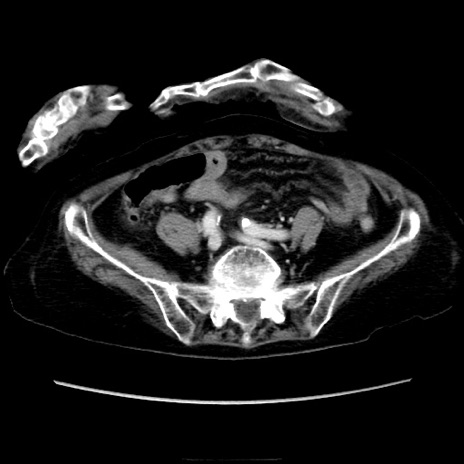

症例40(横断像)

【症例】90歳代女性

【主訴】腹痛・嘔吐

【現病歴】 食欲低下、嘔吐があり昨日他院受診。肺炎と診断され入院となる。入院後より腹部全体に圧痛あり。胃管留置され経過みていたが、症状持続するため、

当院転院となる。

【既往歴】胸椎圧迫骨折、胆石症

【身体所見】腹部:中央に激痛あり、圧痛あり、反跳痛不明

【データ】WBC 17100、CRP 18.82

横断像